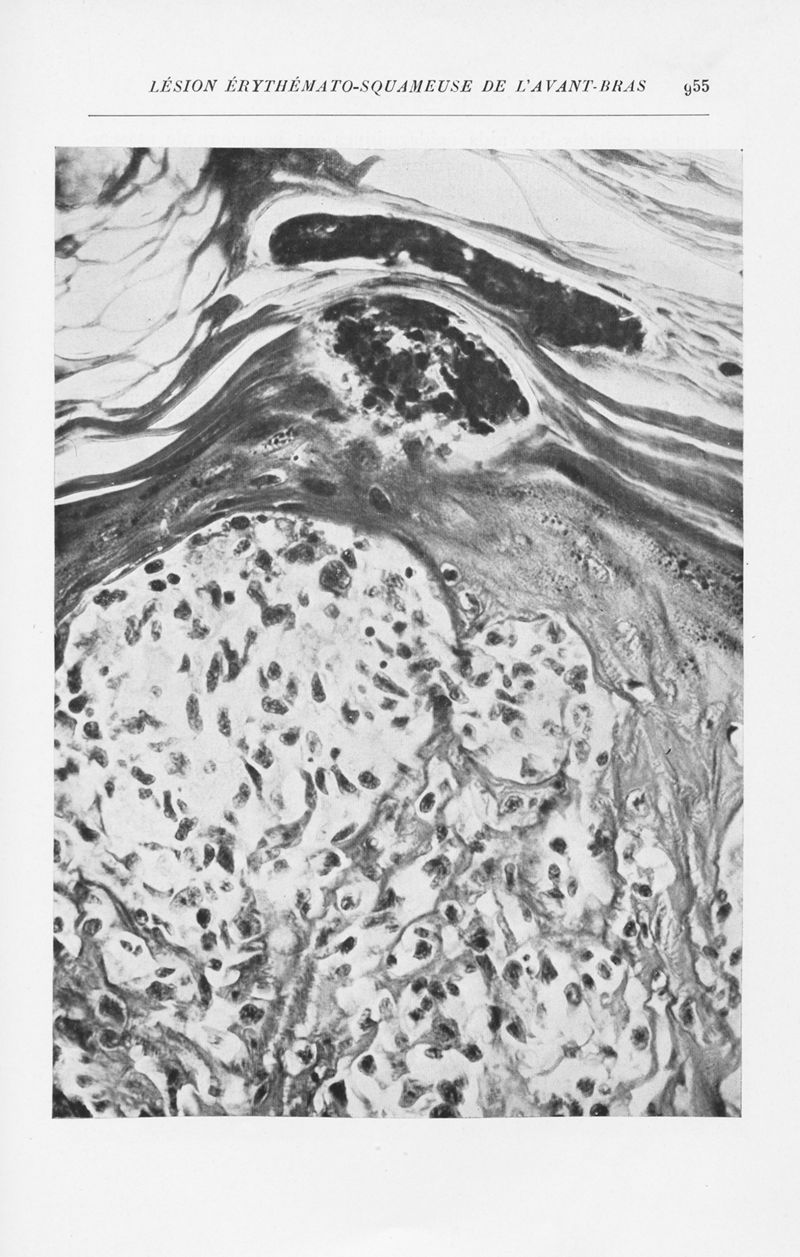

Annales de dermatologie et de syphiligraphie

7ème série, tome X. - Paris : Masson, 1939-1940.